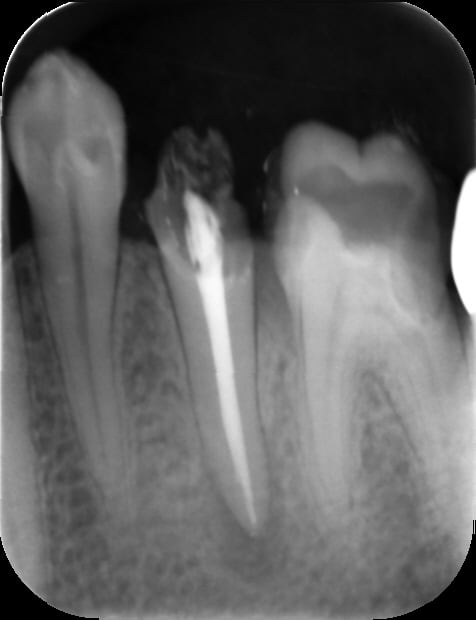

radio de contrôle apres pose d IC la semaine passée , jusque là ça va :-) pas évident sur 1 dent toute seule en terminal

Eri l00uyw - Eugenol